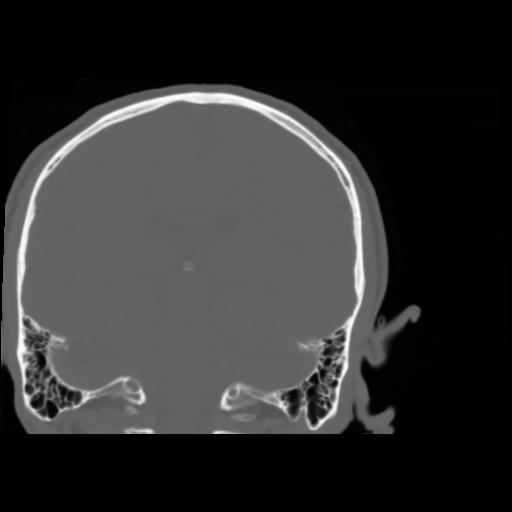

5 CEREBRO,,Coronal,3.000,CEREBRO,Coronal,